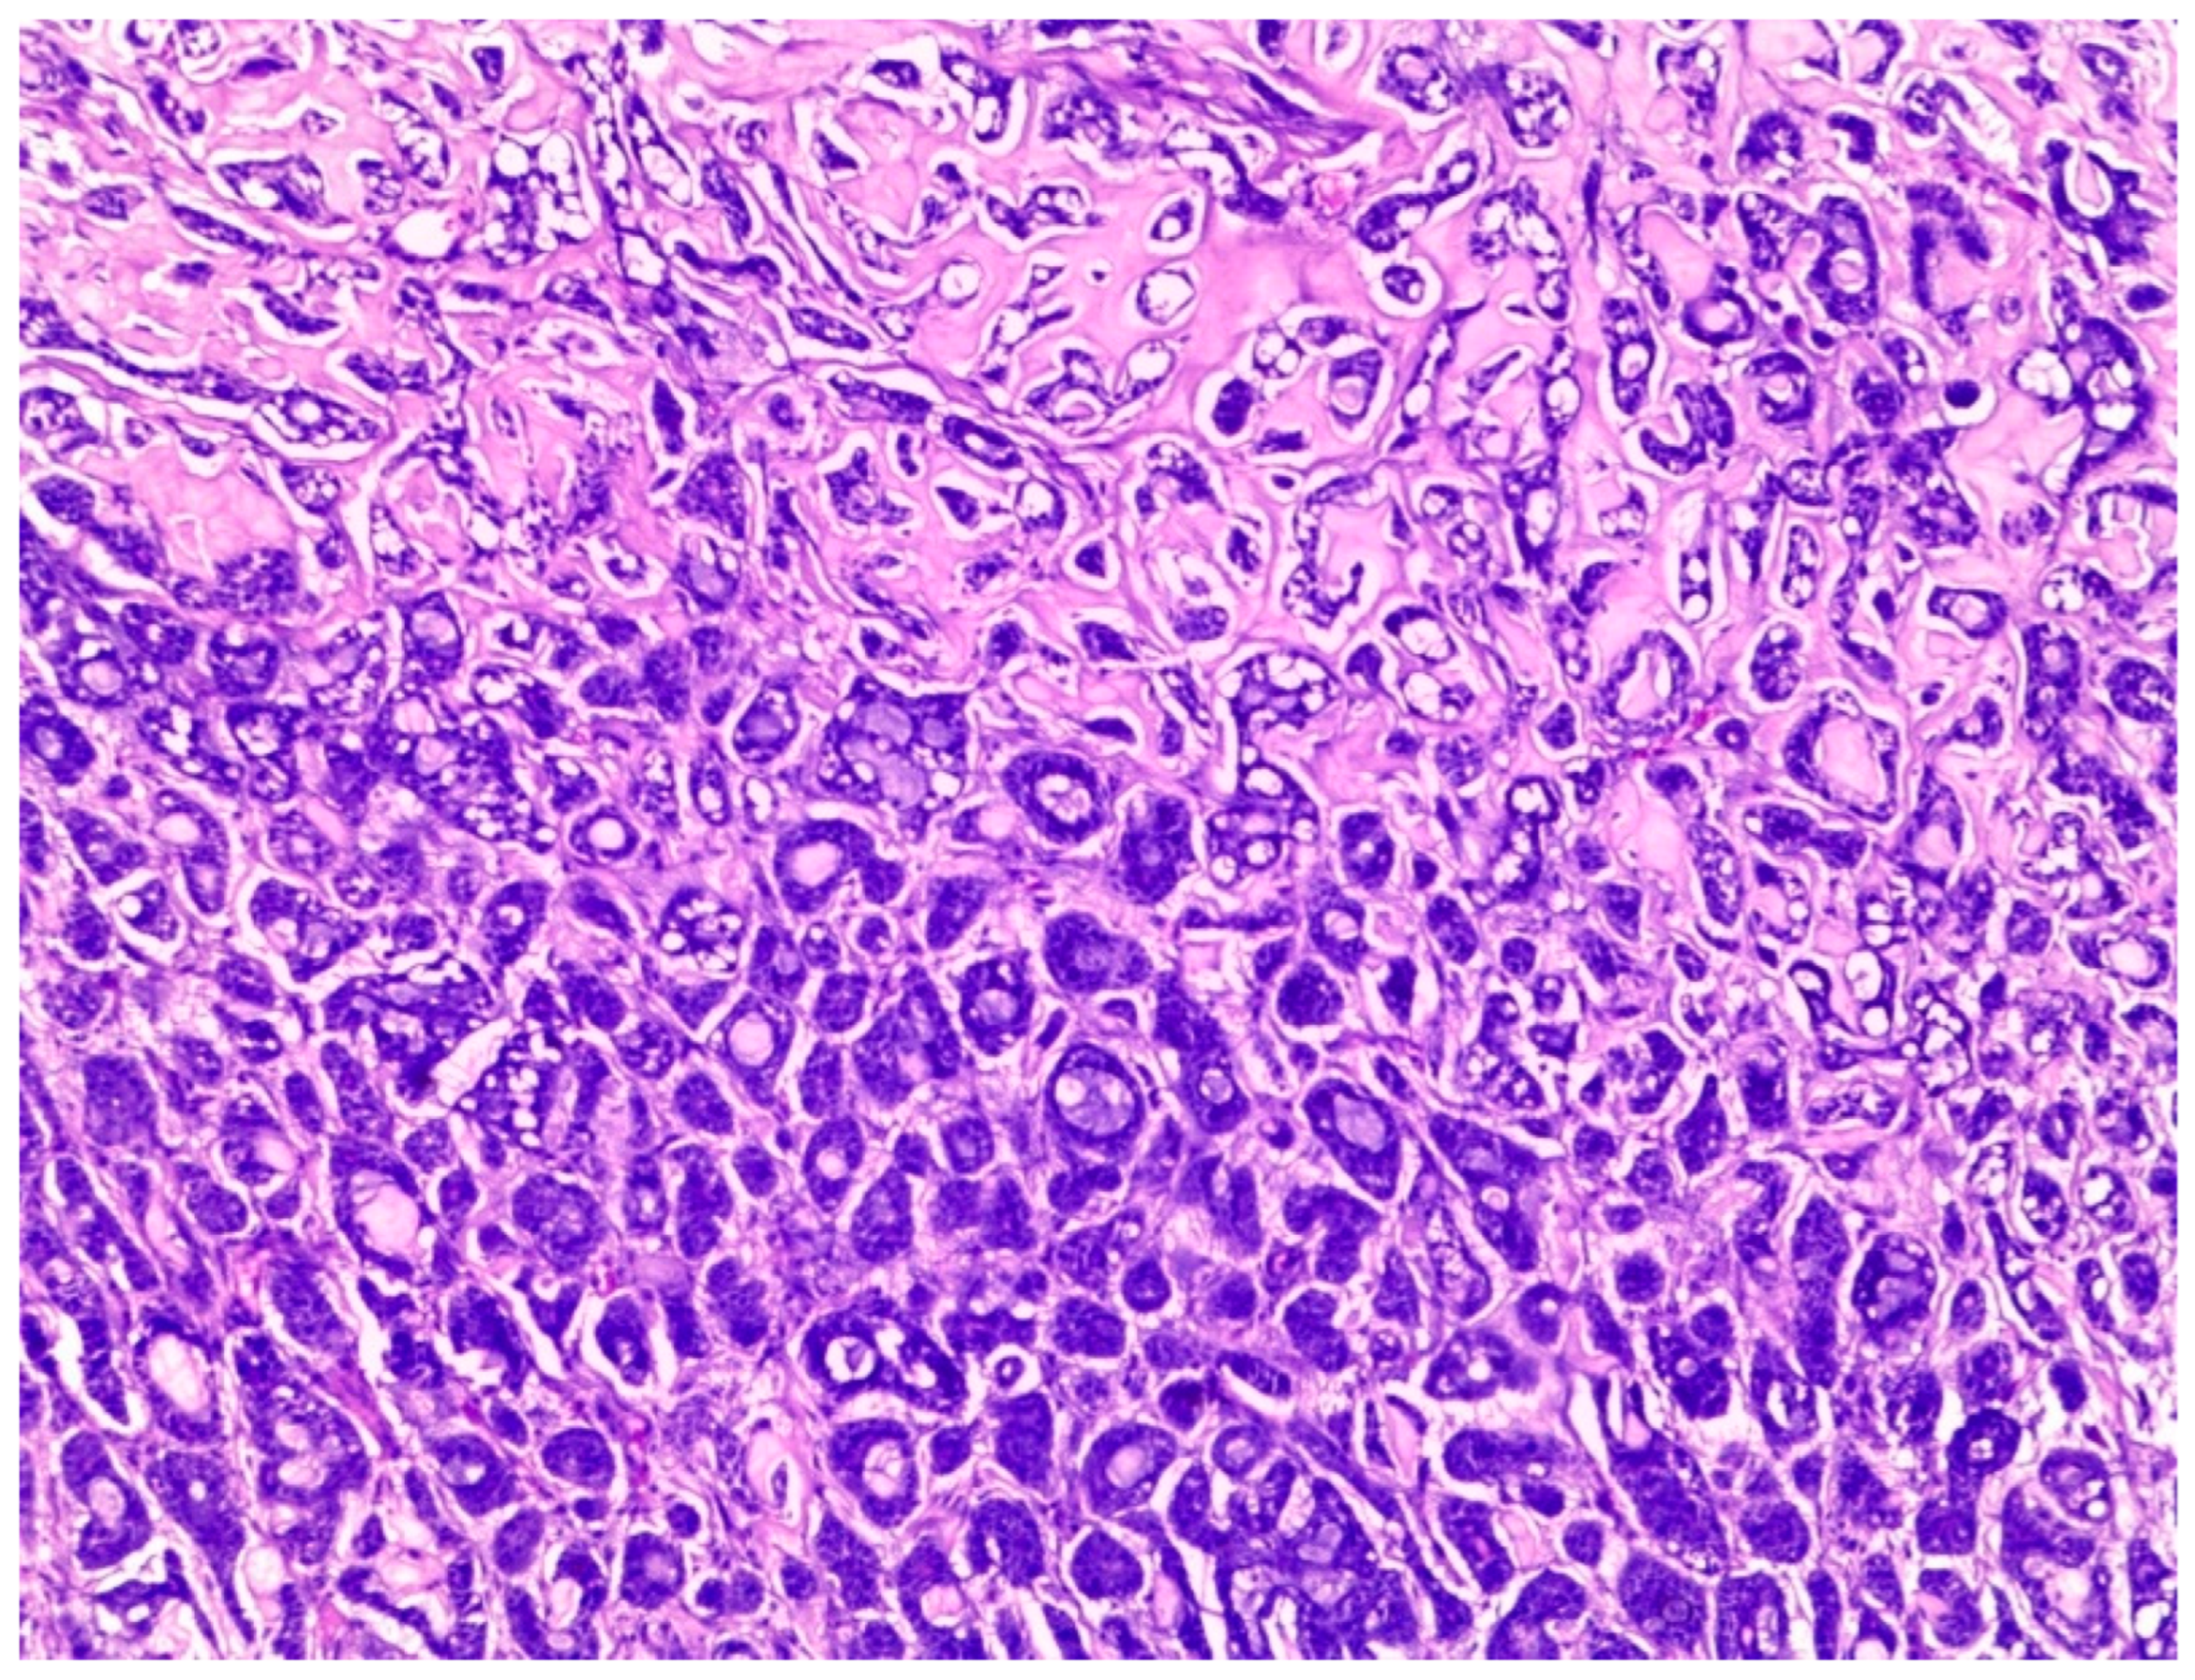

Histologically, salivary nonsolid AdCCs showed biphasic cell populations arranged in alternate cribriform and tubular architectures (Figure 1). The cribriform pattern demonstrated nests of neoplastic cells with hyperchromatic, angulated nuclei arranged in microcystic and macrocystic spaces. These pseudocystic cavities were occasionally filled with hyaline or basophilic mucoid material. The histologic features in the major salivary glands did not differ much from those in the minor salivary glands. However, solid nests of AdCC favored submucosal infiltration in the minor salivary glands (Figure 2, Case #15). Sinonasal AdCC revealed nests of cribriform and solid areas, while extensive hyalinization was recapitulating a jigsaw puzzle-like pattern (Figure 3). The cells of sinonasal AdCC were sometimes basaloid, with dark, hyperchromatic nuclei. The cells were typically arranged in a palisading pattern around the cystic spaces. A few salivary AdCCs revealed basaloid cells arranged in solid growth patterns that were insufficient for diagnosis as high-grade AdCCs. Mammary SB-AdCC revealed areas of cribriform, a solid growth pattern (>90%), and a basaloid appearance, with myxoid or hyalinized stroma. Ductules were present within the tumor islands. Small cysts and pseudoglandular structures were occasionally seen (Figure 4). This variant is characterized by the presence of small, basal-like cells with scant cytoplasm. The basaloid variant was associated with a higher risk of metastasis and a poorer prognosis. All neoplastic cells were positive for IHC SOX10, CK7, CD117, p63, and KI67. The clinical and molecular findings are shown in Table 1. There, all of the AdCC cases had MYB rearrangements detected by fluorescence in situ hybridization (FISH), which is a common genetic alteration observed in AdCC. Specifically, MYB was found to be fused with NFIB and/or KMT2C/KMT2D in AdCC cases from sinonasal and minor SG sites. MYB::NFIB fusion is a well-known molecular alteration that occurs in approximately 30–70% of AdCC cases and has been associated with better prognosis compared to cases without this fusion. On the other hand, MYB::KMT2C/D fusions were less common but have also been reported in cases from salivary and sinonasal AdCCs. Although this is the first study to report this finding, its clinical significance is yet to be fully elucidated. In addition to FISH, some AdCC cases were also analyzed using next-generation sequencing. In Table 1, NGS was performed in several AdCC cases from sinonasal, minor SG, and parotid gland sites. MYB::NFIB and MYB::KMT2D fusions were detected in these cases, which is consistent with the FISH results. Notably, some cases were not analyzable by NGS, which may be due to various reasons such as low DNA quality or quantity. The median score for Group 1 was 70 (IQR: 60–80), the median score for Group 2 was 85 (IQR: 75–90), and the median score for Group 3 was 60 (IQR: 55–70). The results indicate that there was a significant difference between Group 1 and Group 3 (p < 0.05) and between Group 2 and Group 3 (p < 0.05) but not between Group 1 and Group 2 (p > 0.05). This suggests that the solid mammary AdCCs with basaloid features (Group 3) have different characteristics compared to the other two groups.

Figure 2.

AdCC of minor salivary gland with submucosal infiltration by solid nests (H&E stain; magnification ×5).